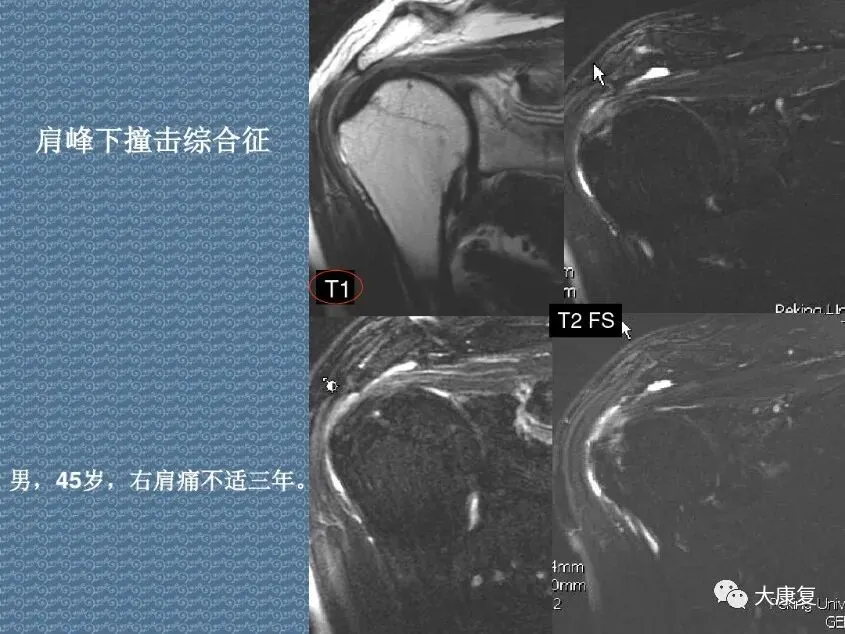

>PPT课件 | 肩关节的解剖结构和特点

PPT课件 | 肩关节的解剖结构和特点